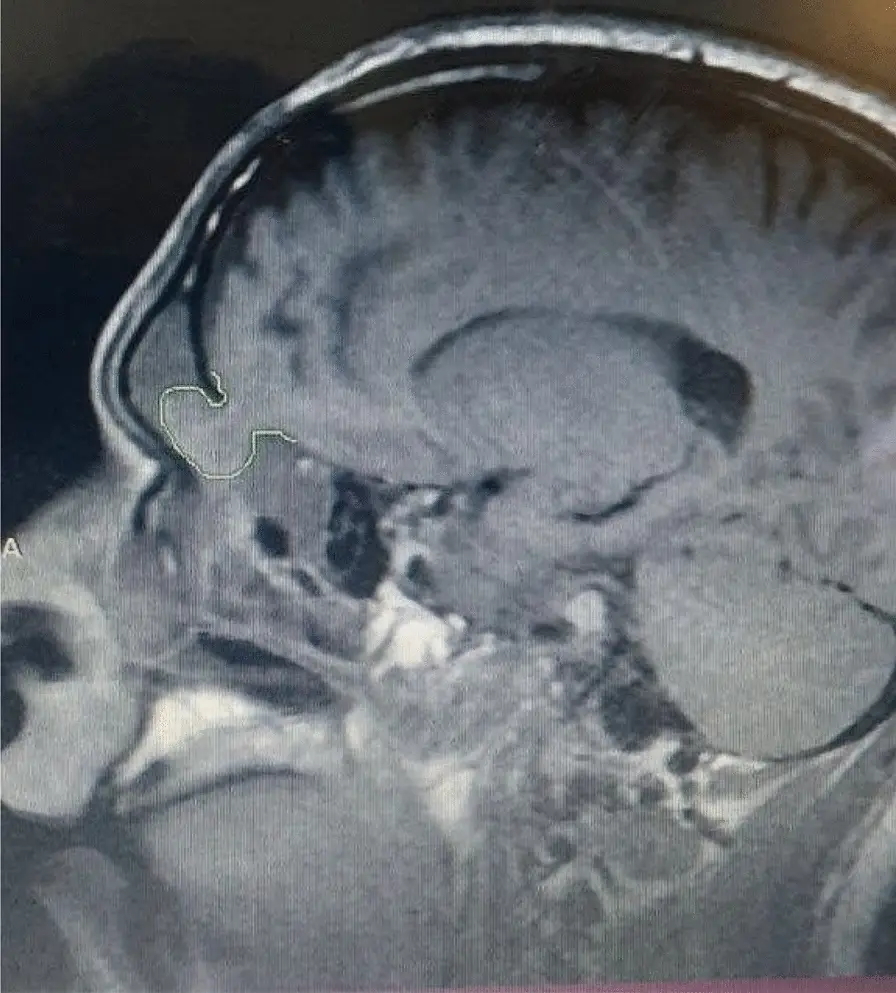

When the man finally sought medical help, scans of his head revealed that he had suffered a fracture at the base of his skull, with brain tissue and meninges (membranes protecting the brain and spine) herniating 'through the skull base fracture' and into the 'subarachnoid spaces in the right hemisphere'.

Put simply, parts of the man's brain was bulging through his right nostril.

The condition is known medically as encephalocele, which is often birth defect where portions of the brain tissue end up outside of the skull. However in this man's case, the condition was caused by head trauma instead of his skull not forming properly.

The case study then notes that the man underwent surgery by a specialist who 'returned the herniated brain tissues to their normal location, repaired the meninges, and reconstructed the skull base with bone cement and bio-glue'. Following the surgery the man was able to recover without any complications.